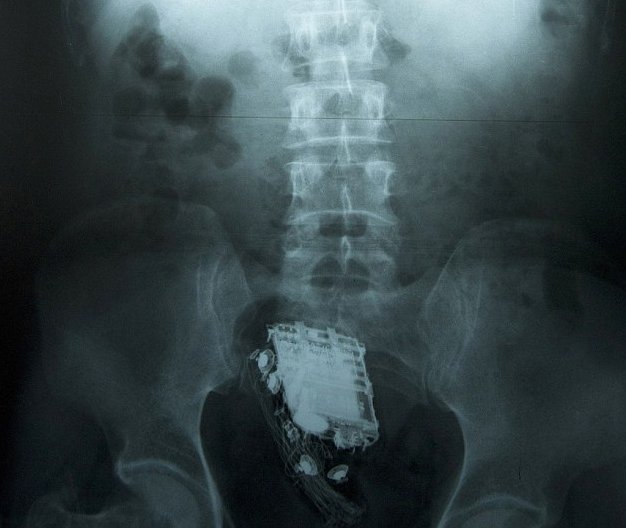

When suspected, an in-depth x-ray, more time-consuming than the one given to regular passengers, is administered on possible packers. If packets are found, these packers will have to wait around to defecate, which doesn’t sound like much fun. At New York’s JFK Airport, that’s done at the “drug loo,” a toilet that automatically washes packets after they’ve been passed.

Cellphone in Rectum

via Daily Mail